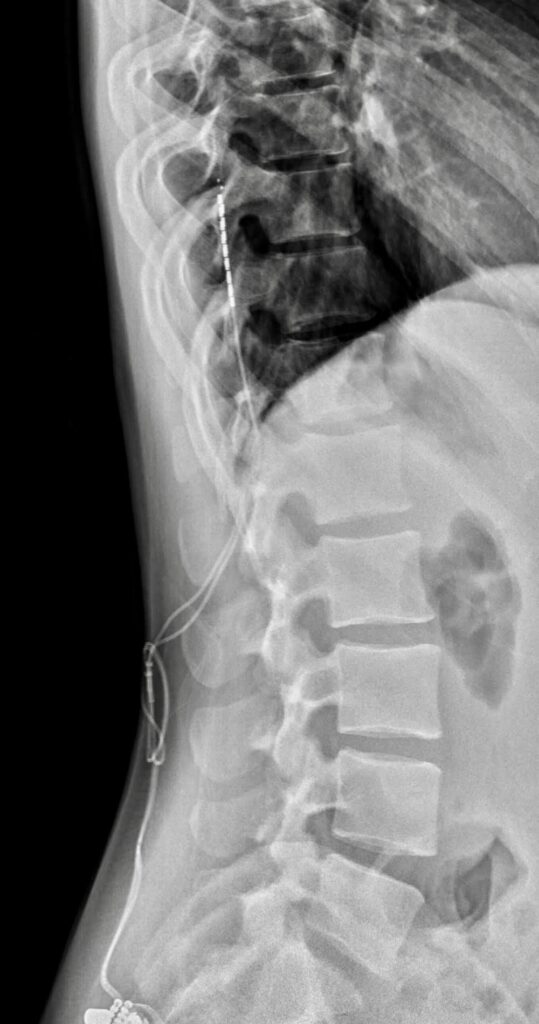

NEUROSTIMOLAZIONE MIDOLLARE

La Neurostimolazione Midollare o Spinal Cord Stimulation permette attraverso sistemi impiantabili percutanei come elettrodi e generatore di impulsi (pacemaker), di creare un campo elettromagnetico attorno al midollo spinale, in grado di interferire sulla conduzione del dolore cronico neuropatico.